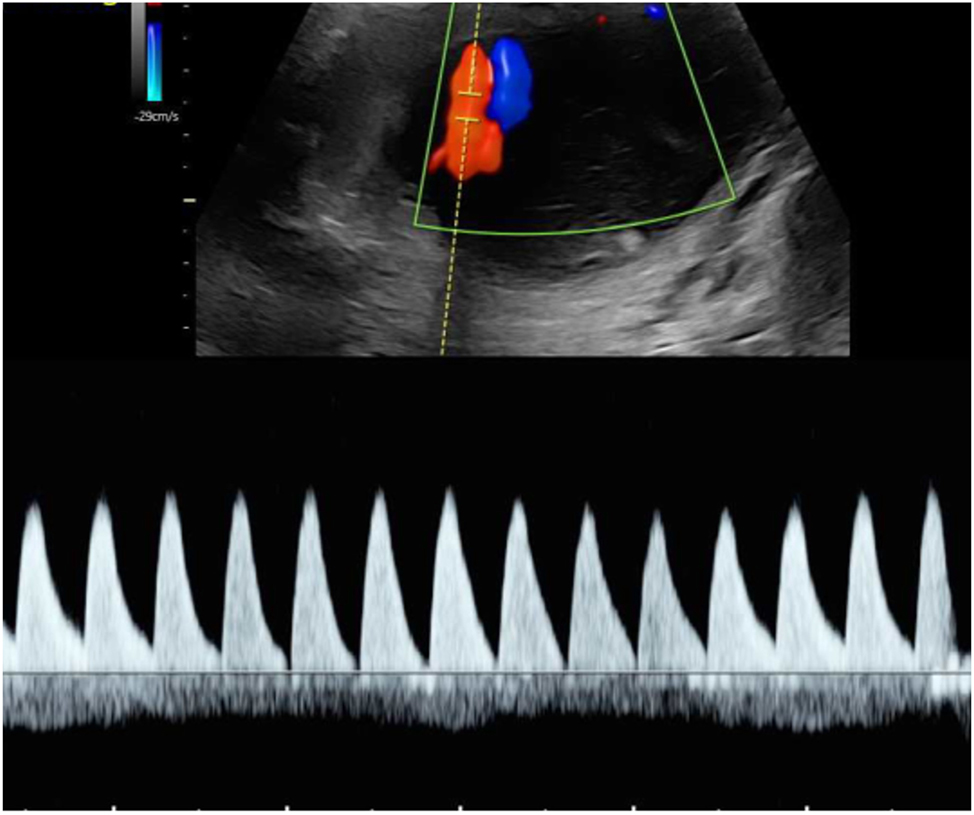

A rare variant of interfetal transfusion in monochorionic twins is twin reversed arterial perfusion (TRAP) sequence, which occurs in approximately 2.5 % of monozygotic twins [7], 8]. This involves reversed perfusion of the commonly singular umbilical artery of the affected twin via a large-caliber arterio-arterial anastomosis, resulting in disrupted development of the heart and the upper body (Figure 6). While the affected fetus has no chance of survival, the healthy pump twin is also at risk due to excessive strain on the heart [65].

Sonographic image of a rudimentary TRAP fetus (22 + 4 weeks of gestation) with typical reversed arterial perfusion in the singular umbilical artery.

Diagnosis can be made by demonstrating reversed perfusion in the umbilical artery of the TRAP fetus using Doppler sonography. Monitoring the ductus venosus of the pump twin can be used to detect cardiac decompensation in a timely manner.